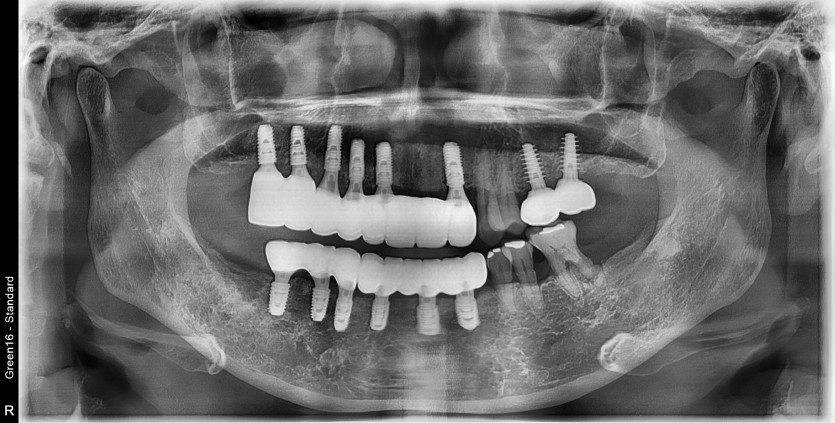

만 56세 상 하악 임플란트 증례

상 하악 임플란트 증례입니다.

12개의 임플란트로 완성하였습니다.

(상악 6개, 하악 6개)